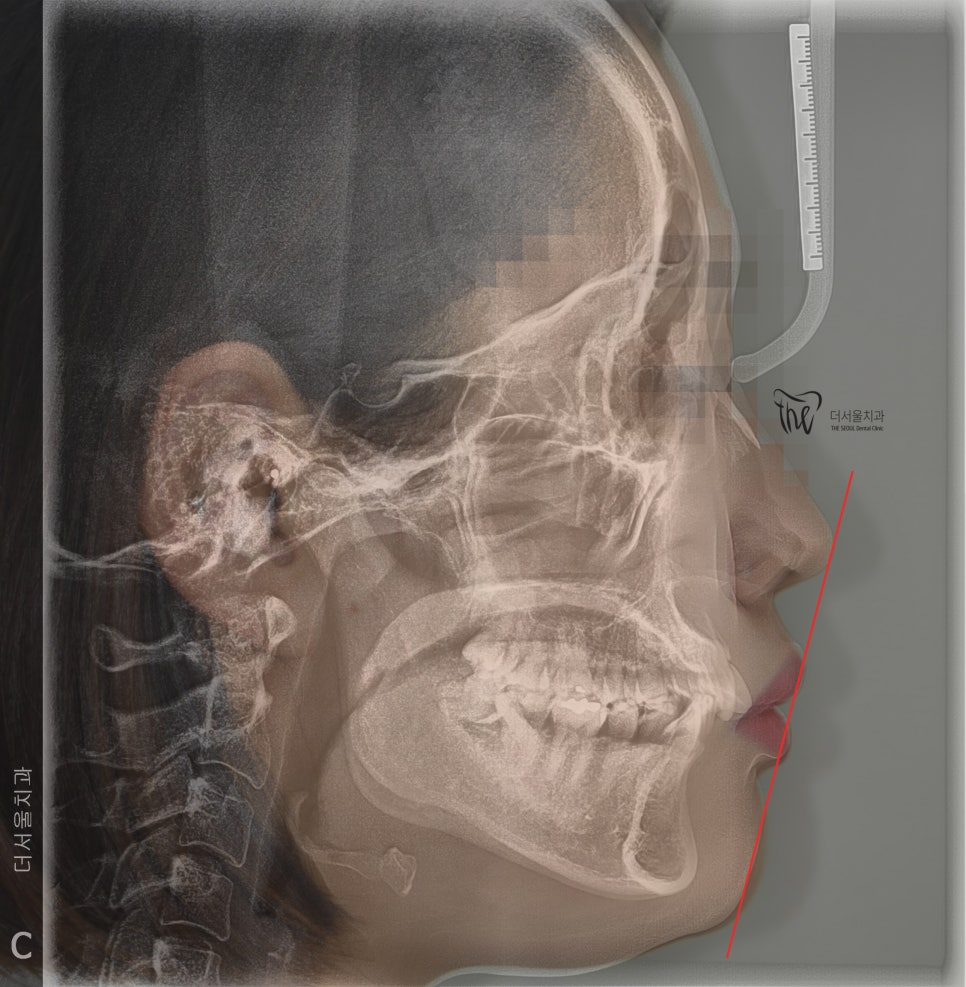

부정교합 2급 이라는 것은, 하악보다 상악이 더 전방에 위치되거나 또는 상악의 치아들이, 하악 치아들보다 더 앞쪽에 위치되어 있는것을 뜻하며

증세를 갖고 계셨던 분의 임상 증례를 보여드립니다. 교정 치료를 통해서 2급 부정교합이 개선 되었으며 치료를 끝으로, 턱 끝에 보형물